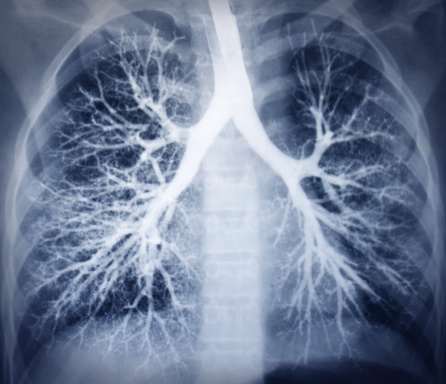

Bradypnea is the medical term for a reduced rate of breathing. The criteria for this is when a person’s breathing rate is less than 12 breaths per minute. Bradypnea can be due to a number of underlying reasons or medical conditions, or it can even occur during a normal sleep. However, if bradypnea occurs while ...click here to read more